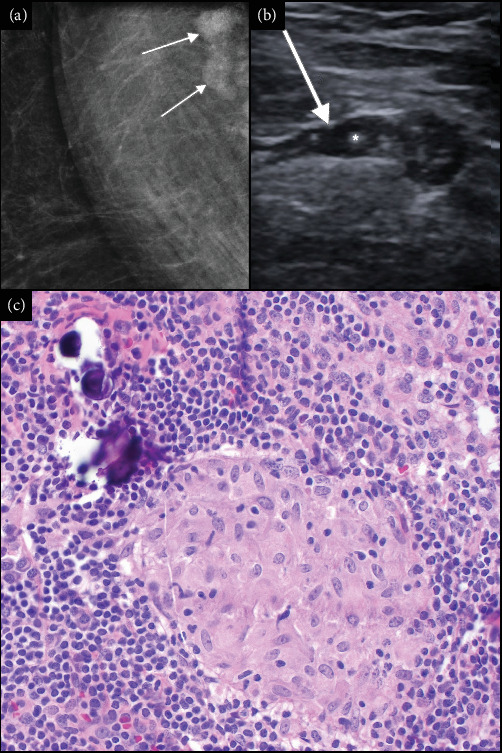

Purpose: Sarcoidosis is a systemic inflammatory disease associated with ocular involvement in 20%-30% of cases. The current gold standard for detecting sarcoidosis is computed tomography of the thorax, which is 73% sensitive. Definitive diagnosis necessitates biopsy, with Schaumann bodies and non-necrotizing granulomas serving as key pathological hallmarks. Observations: Our patient, a 44-year-old White female, presented for a second opinion on her bilateral chronic intermediate uveitis with intractable chronic cystoid macular edema of the left eye. Our clinical suspicion for sarcoidosis was high, but the computed tomography thorax scan did not show any abnormal findings. A routine mammogram completed 4 weeks prior to our initial evaluation showed axillary lymph node enlargement with calcifications. Subsequent biopsy was consistent with sarcoidosis. Treatment with mycophenolate mofetil resolved the uveitis and macular edema. Conclusions and Importance: The diagnosis of sarcoidosis can be challenging due to nonspecific ocular signs and the potential for falsely negative findings on imaging. This case highlights the importance of patient education and self-surveillance regarding the characteristic systemic symptoms of sarcoidosis, which commonly involve the lungs, eyes, skin, joints, etc. Our report demonstrates the significance of maintaining a high level of suspicion for sarcoidosis in patients with characteristic ocular findings, even when initial imaging results are negative or inconclusive.